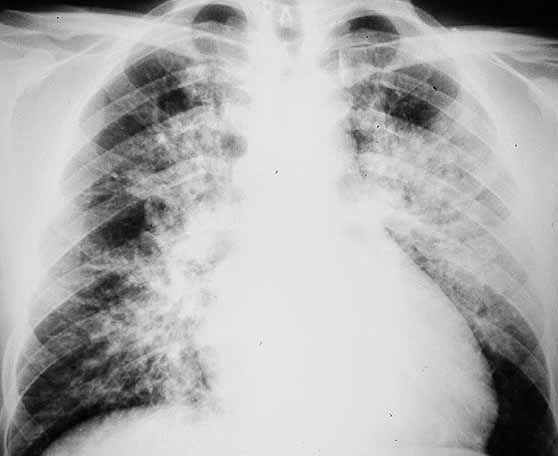

Figura 1. Radiografía simple de tórax al ingreso del paciente. No se observan alteraciones significativas.